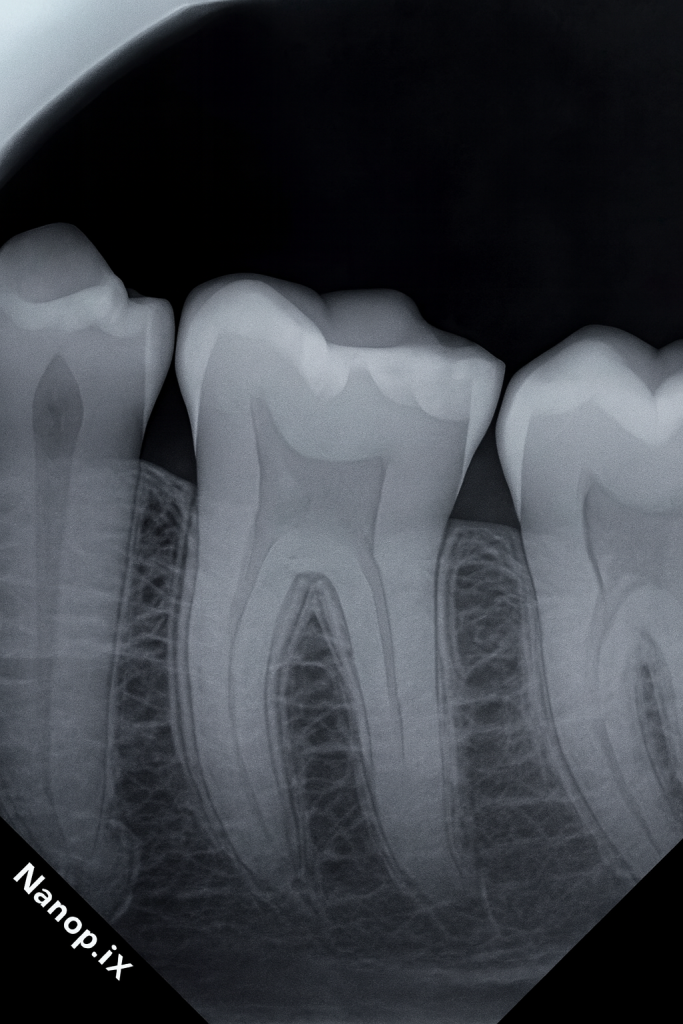

2. DIAGNOSIS

- Tooth: Mandibular first molar

- Primary issue: Proximal caries with lost contact

- Symptoms: Food packing, dull discomfort during chewing

- Radiographic findings: Localized radiolucency in distal box; enamel margins intact; PDL normal

- Pulp: Vital

- Periodontal status: Stable, localized gingival irritation due to food impaction

Final Diagnosis: Class II distal carious lesion with open contact.